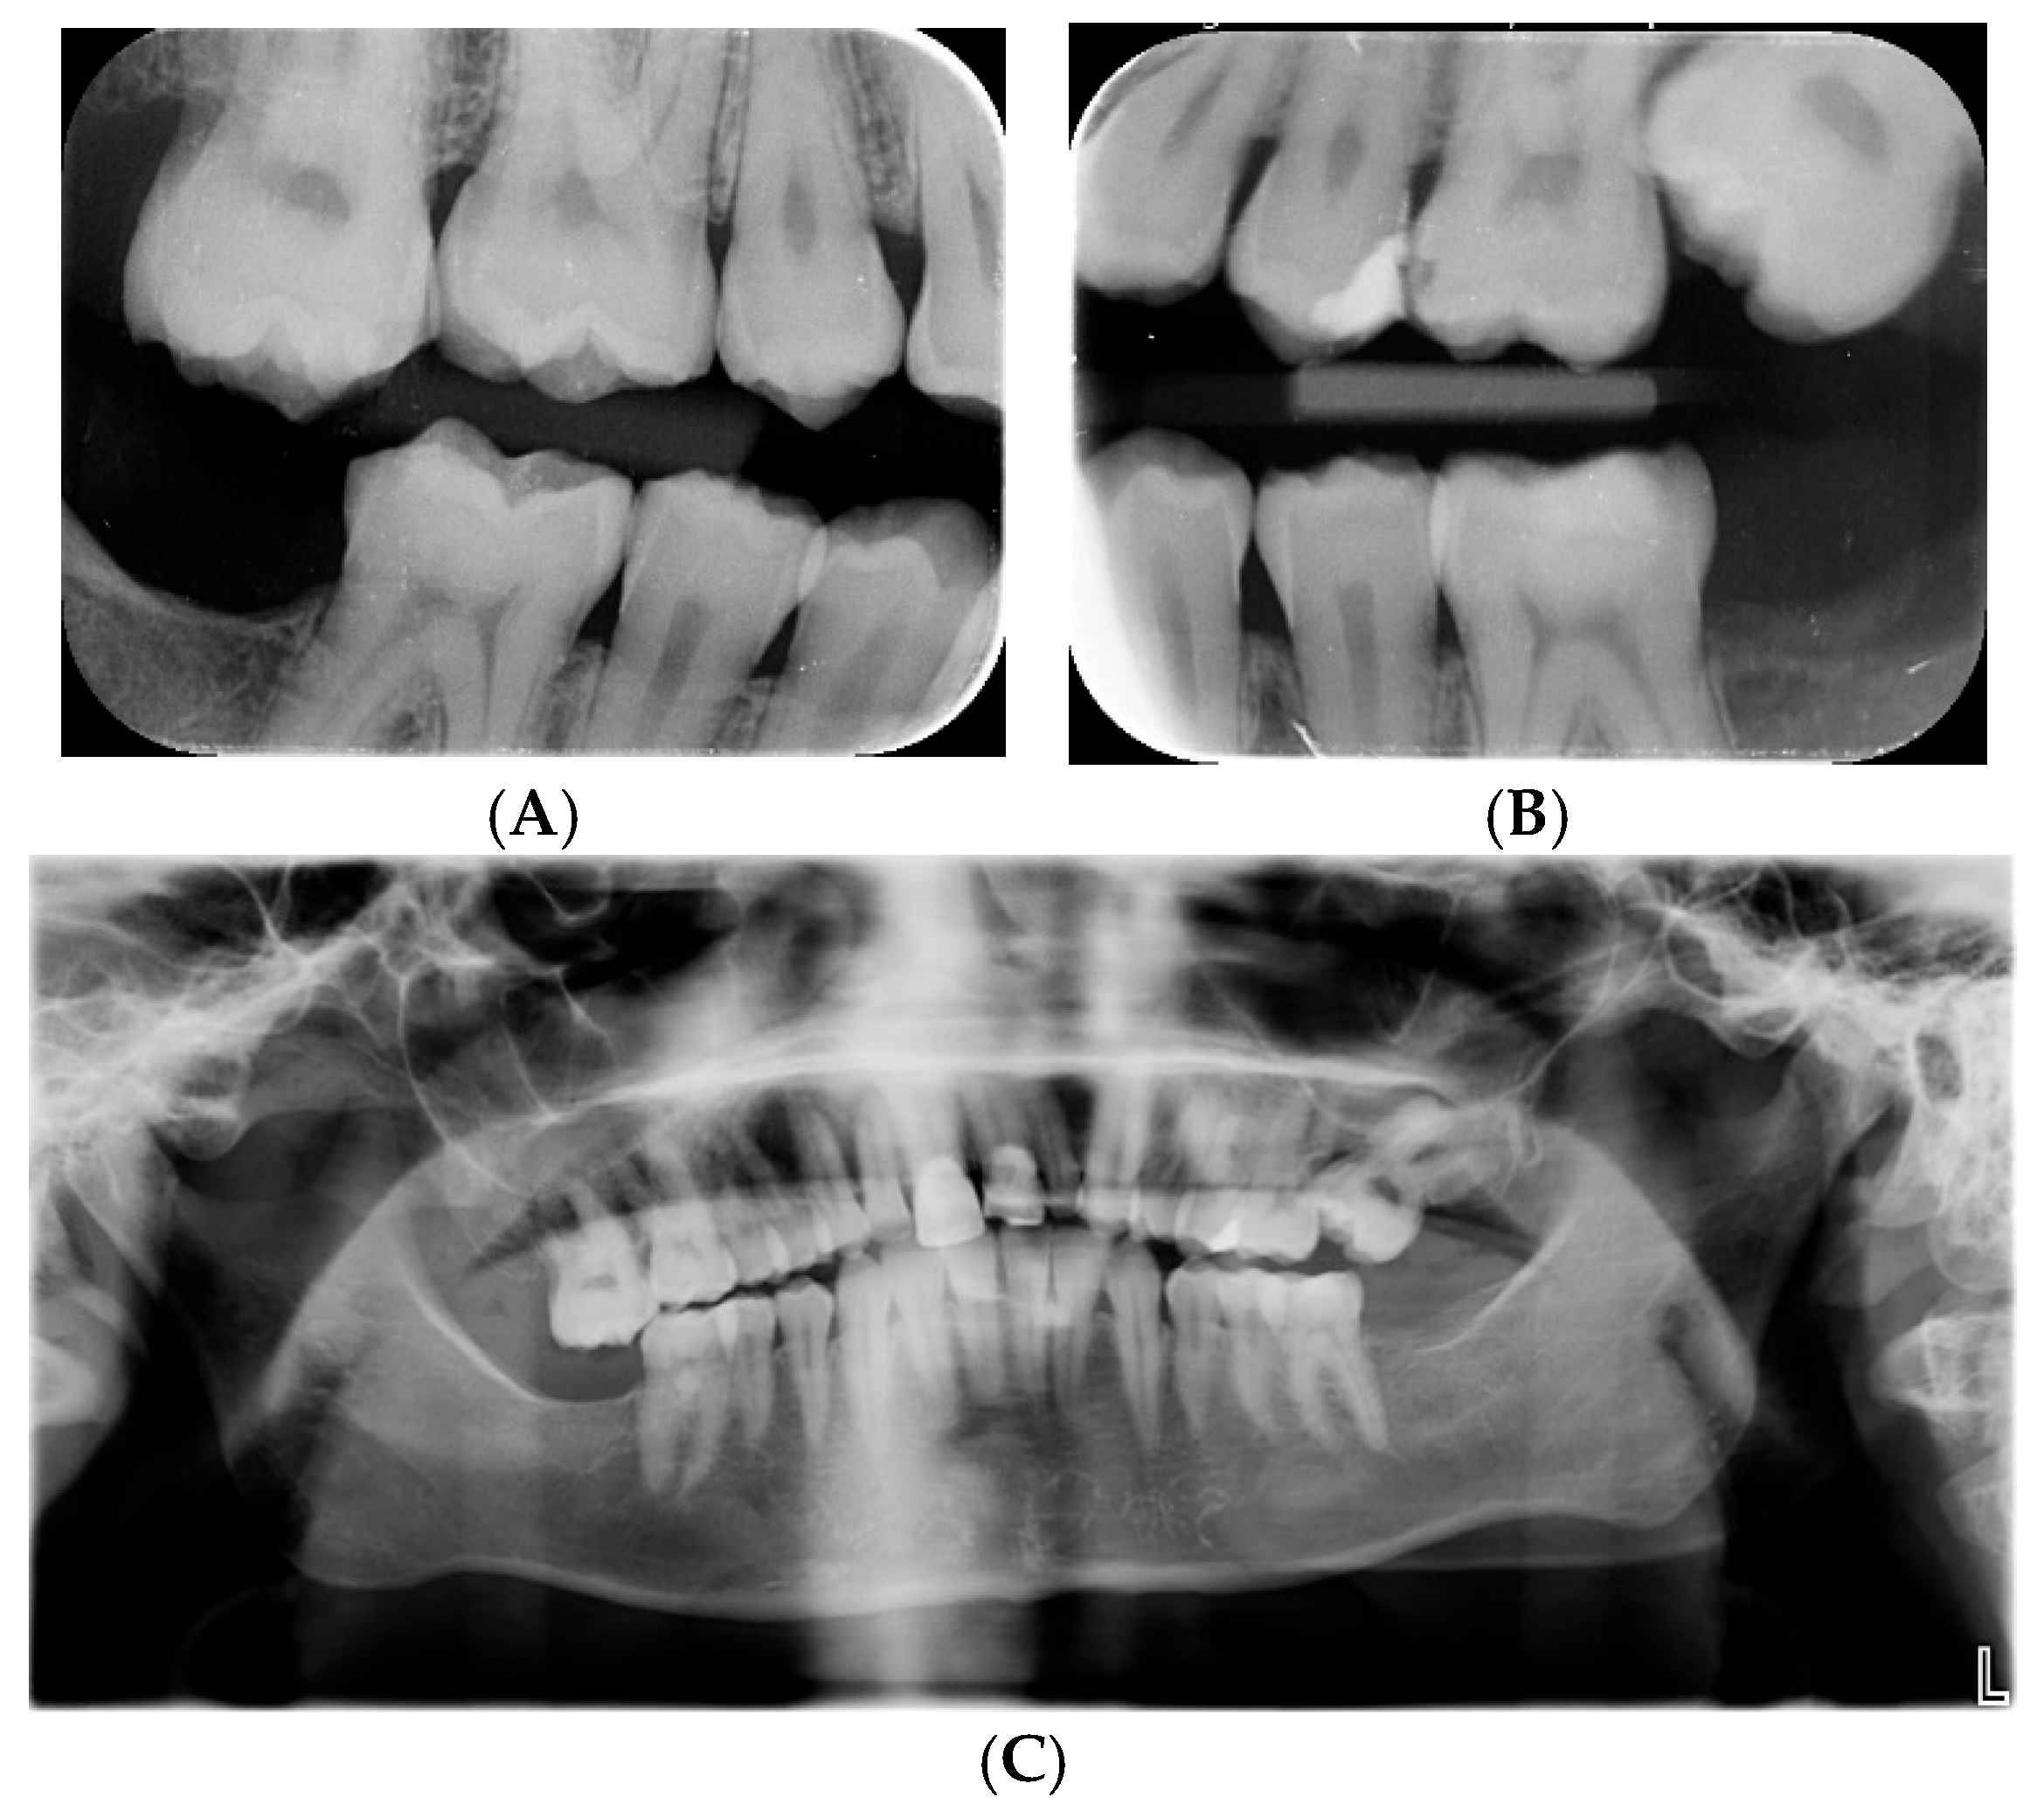

As the teeth phenotype was not among the referral symptoms and one of the variants was a missense variant, the referring clinician was contacted to confirm the dental findings. Clinically, the permanent teeth showed lusterless enamel with white, yellow, and brown opacities. The teeth were crowded, with an overjet of 12 mm, bilateral distal occlusion, and a deep incisor overbite measuring 5 mm. Teeth 11 and 21 had composite restorations (Figure 1). Tooth 27 was ectopically positioned and caused resorption of tooth 26, as seen on radiographs for all teeth. Teeth 18 and 28 were congenitally absent. Teeth 38, 37, 47, and 48 were removed under general anesthesia at the age of 20 due to ectopic positioning of 38 and 48 leading to pathological resorption of the adjacent teeth 37 and 47 (Figure 2). The contrast between enamel and dentin on the radiographs was markedly reduced, indicating poor enamel mineralization. The combined dental, clinical, and radiographic findings are compatible with hypomature amelogenesis imperfecta together with tooth agenesis and eruption defects. See Box 1 for explanation of different types of mineralization defects.

Figure 2. (A,B) Bitewings radiograph at the age of 18 years shows caries 26 and ectopic 27, yet no resorption of 26. Low contrast between enamel and dentin is observed. (C) Panoramic radiograph at the age of 28 years shows movement artifact as well as an ectopic 27 causing resorption distally on 26. Teeth 18 and 28 are congenitally absent, but 37, 38, 47, and 48 were removed at the age of 20 due to ectopic positioning and resorption.